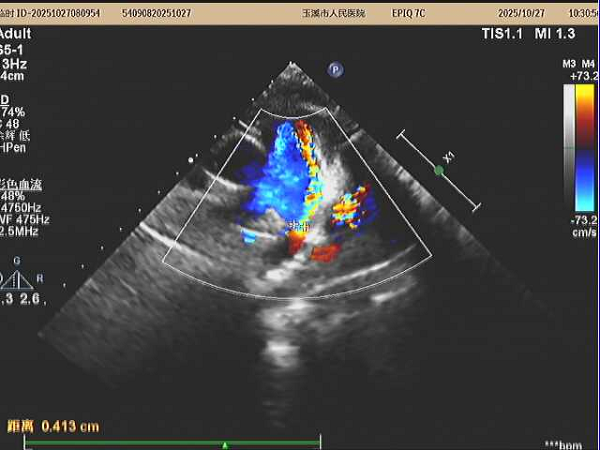

患者为4岁男性患儿,体检发现先天性心脏病:动脉导管未闭,分流4.3mm,且左心房已经扩大,来我院就医希望能得到进一步及时诊治。

在张智伟教授指导下,玉溪市人民医院心内科团队手术过程中,精准定位动脉导管分流位置,将生物可降解封堵器成功植入,实现了对分流的有效封堵。术后超声评估封堵器周围无残余分流,封堵器占位良好。